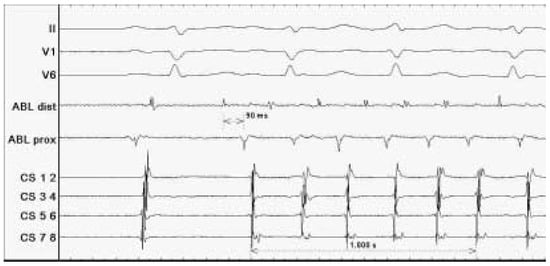

Case description A 70-year-old former athlete complained about a twenty-year history of paroxysmal atrial fibrillation with onset at rest and during the night, which became persistent in the last three years [...]